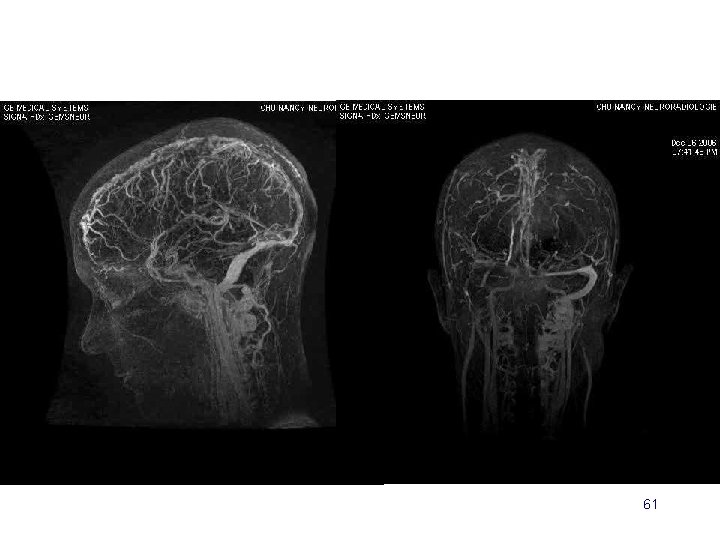

Angio IRM (ARM) 3 D PC 2 D TOF veineux 3 D Gd+ 58

• 2 D TOF veineux – Rapide – C– Faux + • 3 D Gd + – Rapide ++ – Sinus et veines corticales 60

61

Evaluation de la séquence d’ARM dynamique 3 D dans le diagnostic et le suivi des thrombophlébites cérébrales Tisserand M (1), Rodrigo S (2), Foscolo S (1), Naggara O (2), Schmitt E (1), Anxionnat R (1), Meder JF (2) et Bracard S (1) CHU Nancy, Service de Neuroradiologie Diagnostique et Thérapeutique (2) CH Sainte Anne Paris, Département d’Imagerie Morphologique et Fonctionnelle 62

Conclusion La séquence d’ARM 3 D dynamique Fournit des images de bonne qualité Imagerie parallèle : résolutions temporelle et spatiale Permet une évaluation du système veineux cérébral Acquisition rapide ( 2 minutes ) En concordance avec les autres séquences Informations dynamiques Séquence ARM de référence au diagnostic La seule au suivi ? 71